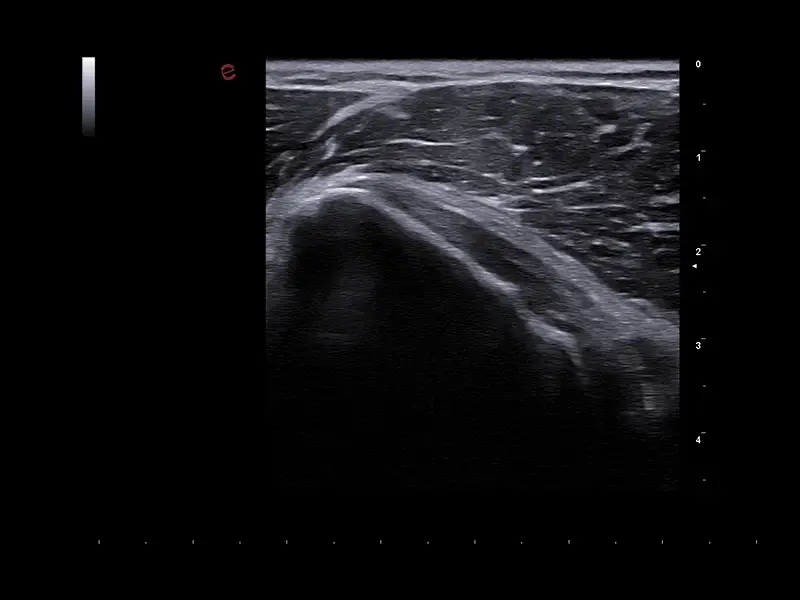

S MyLab™ A50 získáváte možnost provádět široké spektrum vyšetření, včetně jater, srdce, gynekologie a porodnictví, cév, prsu, štítné žlázy, muskuloskeletálního systému, urologie a pediatrie.